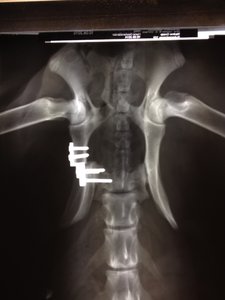

Ich hab mir mal die Röntgenbilder schicken lassen.

Hier sieht man mal den Spalt der nach dem Sturz entstanden war man sieht auch, wie sehr der Beckenknochen in Richtung Wirbelsäule gedrückt wurde :shock:

Hier mal im direkten Vergleich: direkt nach der OP

So sieht es jetzt aus. Knochenmaterial noch etwas "dünn", aber jetzt schon soweit, dass sie absolut nicht mehr humpelt oder hoppelt und auch wieder komplett belastet.